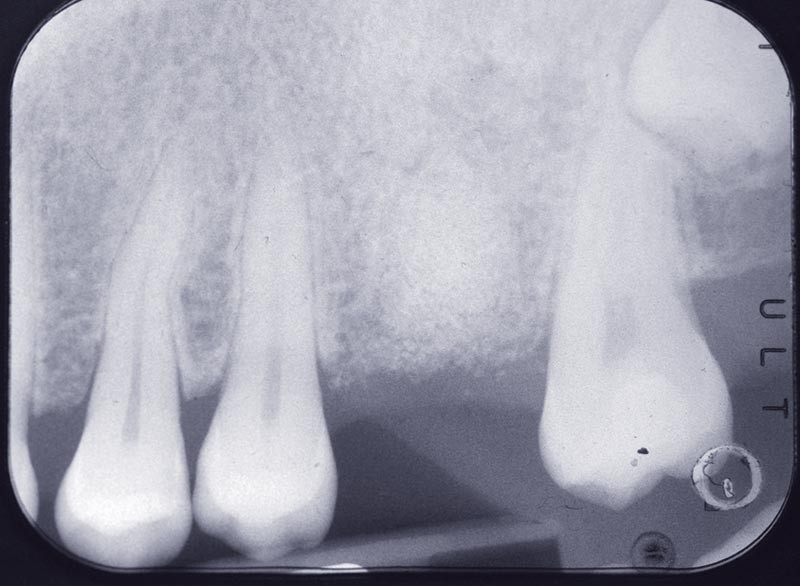

La patiente se présente au cabinet pour une fistule vestibulaire sur la 26. Elle avait subi une résection apicale qui n’avait pas eu de succès et avait provoqué une résorption de la corticale vestibulaire de l’alvéole. Le plan de traitement proposé prévoit l’extraction de la dent, le comblement de l’alvéole et du défaut avec la technique de « socket preservation » (fig. 1).